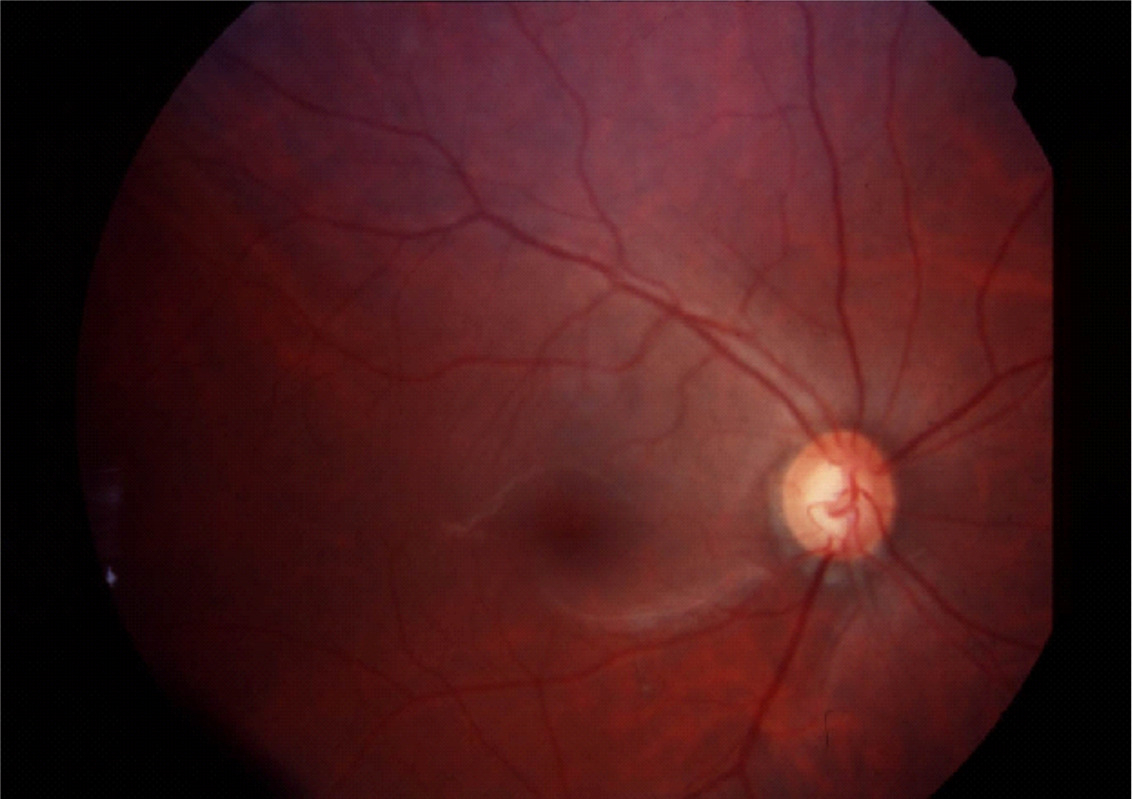

Fundus photography records digital photographic images of the back of the eye (the fundus). Specific parts of the fundus can be photographed such as the optic nerve and macula. Fundus photography compliments OCT in that it provides true color images of the different structures.

Normal Optic Nerve

Glaucomatous Cupping

Fundus photography allows documentation of changes to the optic nerve that occur glaucoma including cupping, disc hemorrhages, atrophy, and loss of the nerve fiber layer. Certain filters can be used to enhance the visualization the nerve fiber layer.

An example of an optic nerve with glaucoma damage imaged with both fundus photography and OCT and compared to the visual field in order to demonstrate the strucure-function relationship.

The lower half of the optc nerve has early damage, and this correlates with the small superior scotoma seen on the visual field test.